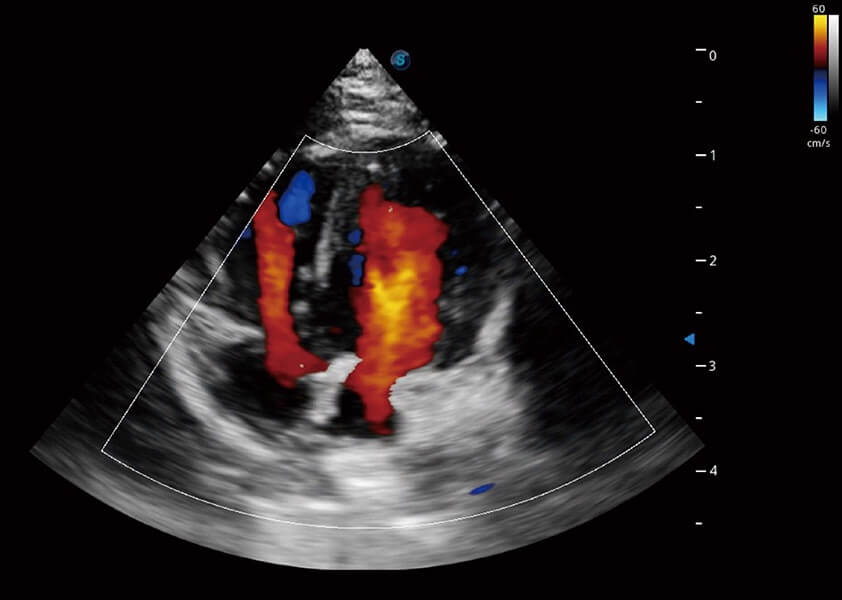

ProPet 60 作為一款高端臺(tái)式動(dòng)物超聲設(shè)備,為動(dòng)物醫(yī)生的日常診斷提供了一系列貼合動(dòng)物臨床需求、解決臨床實(shí)際問(wèn)題的高級(jí)成像功能。憑借全系列高清探頭,滿足醫(yī)生對(duì)腹部、心臟、生殖、淺表、肌骨等成像的所有需求,切實(shí)幫助您提升檢查效率,提高診斷信心。